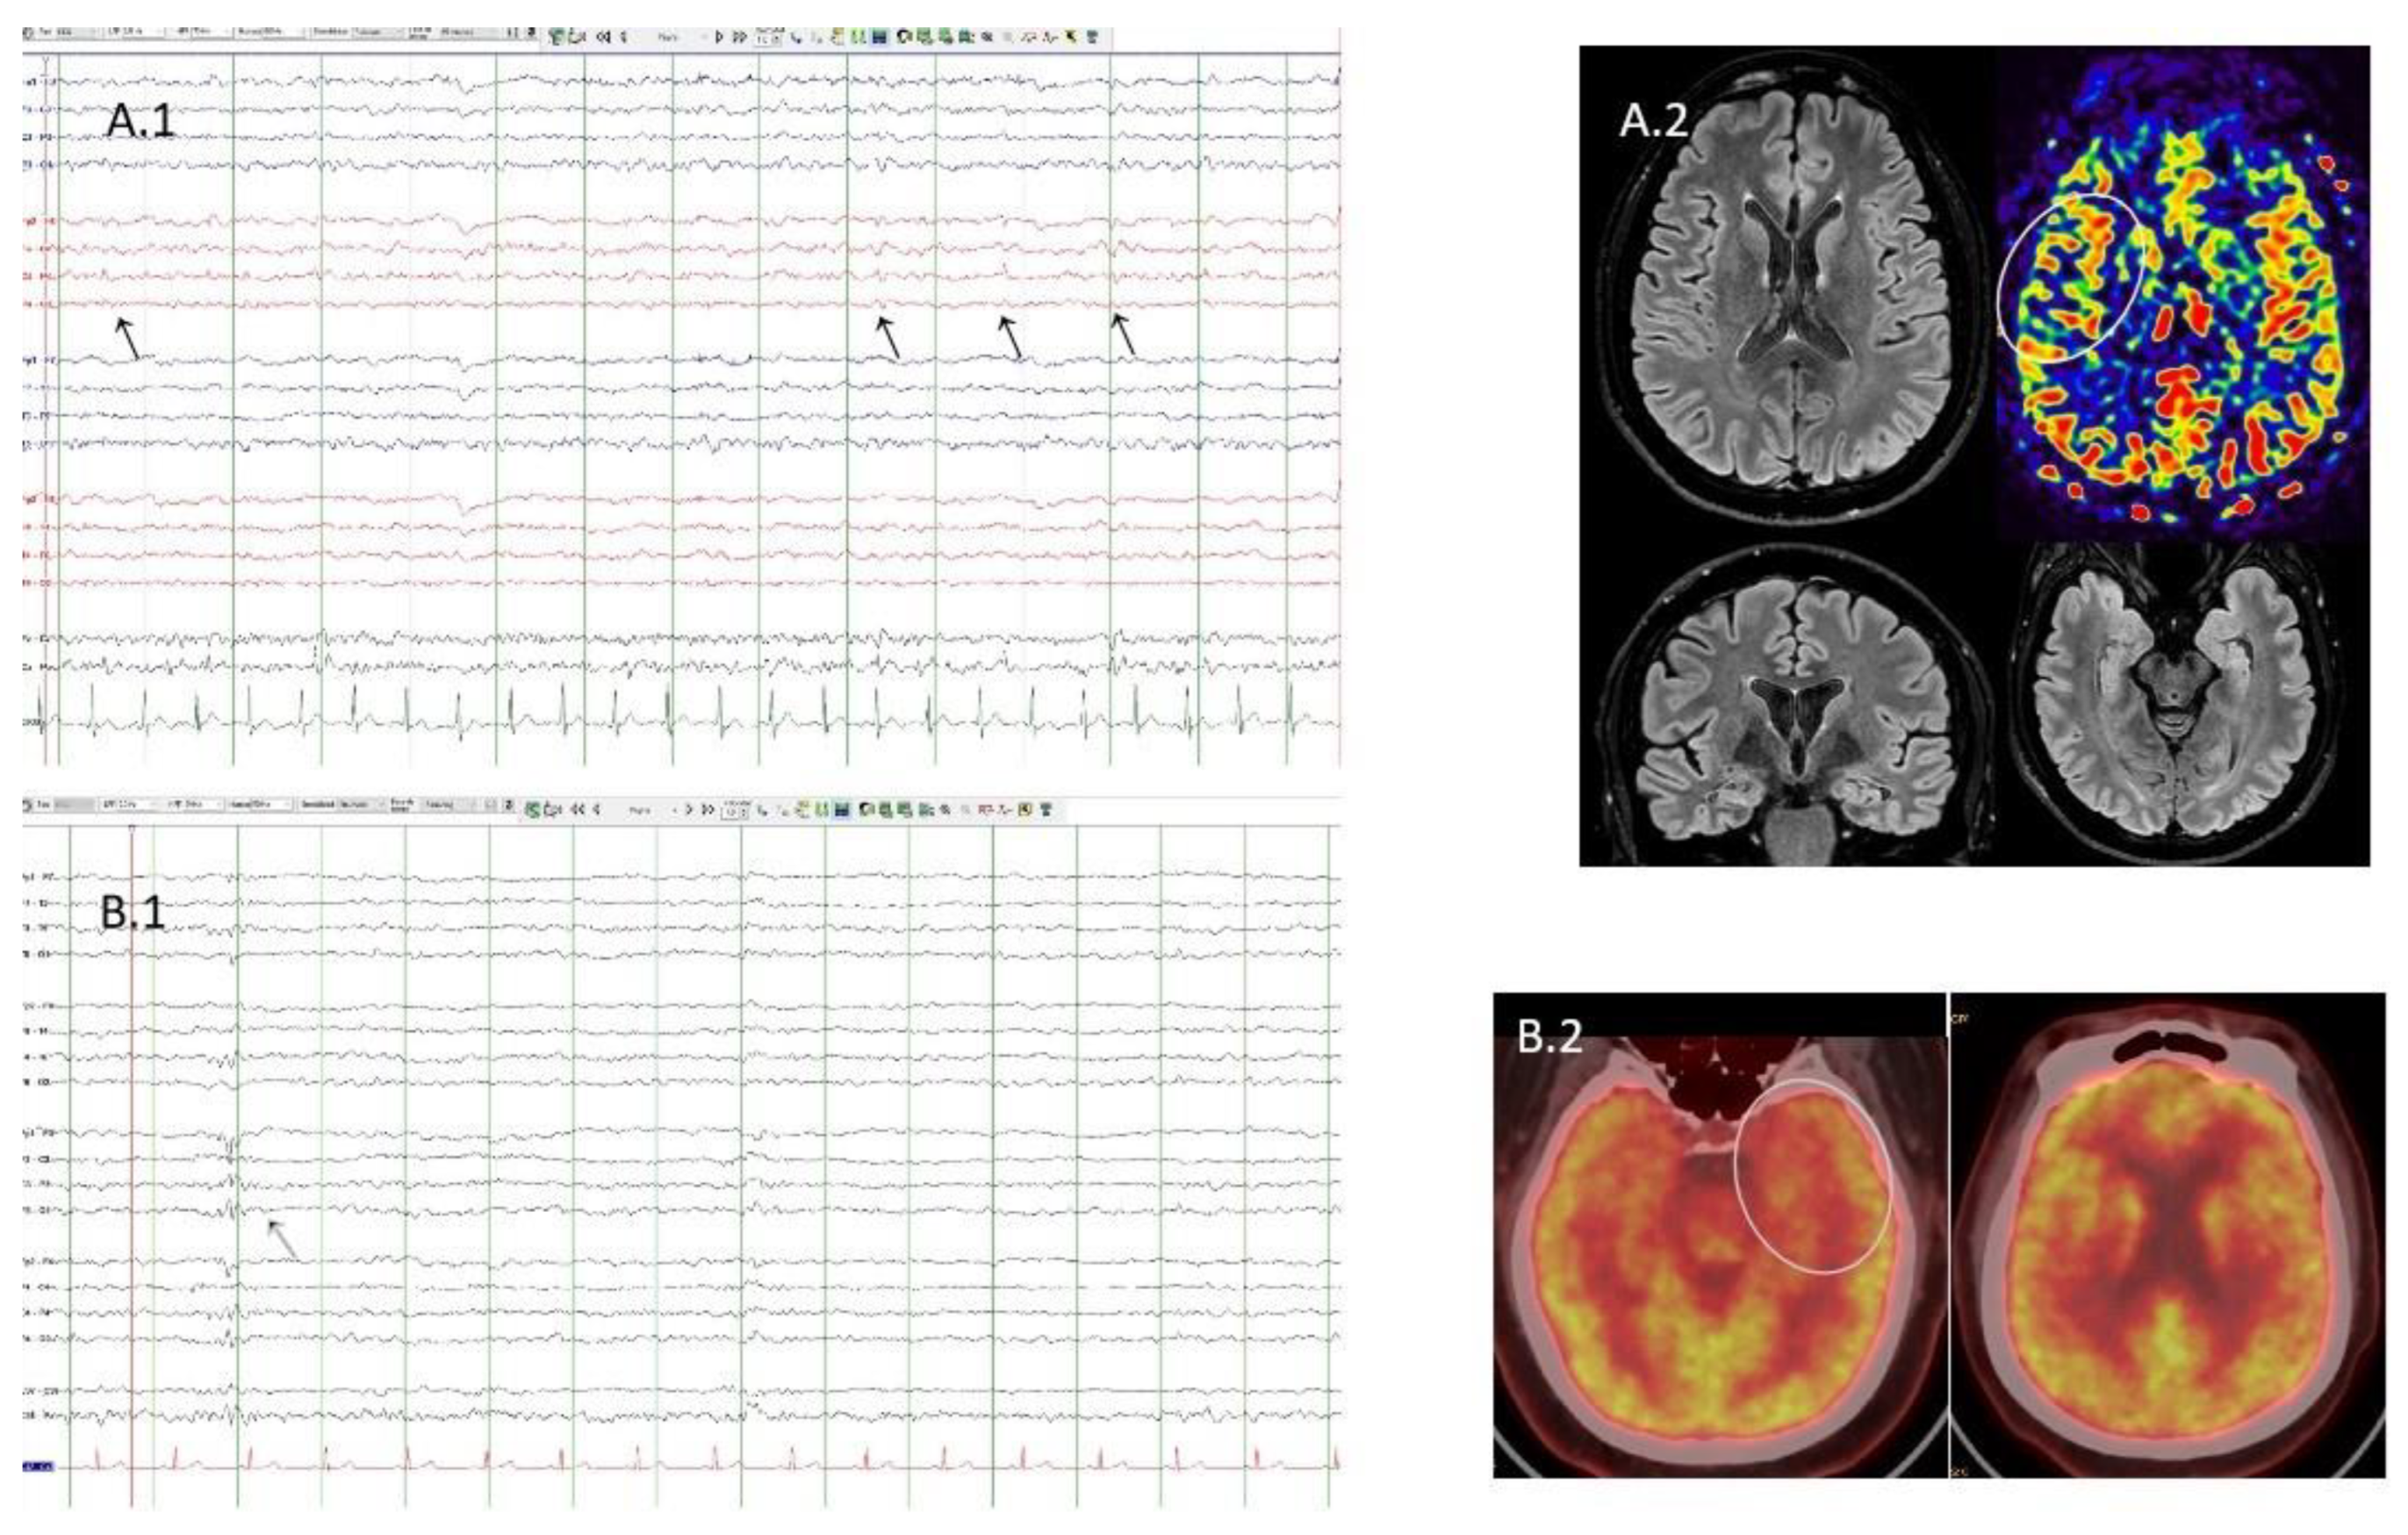

A1. Case 4. EEG with partial sleep deprivation. Bipolar montage. Presence of interictal epileptiform discharges (black arrows) located in the right fronto-central area. A2. Case 4. Flair sequences showing normal structural MRI. Arterial spin labelling sequence shows discrete hypoperfusion in the right operculo-insular area (white circle). B1. Case 1. Sleep EEG. Bipolar montage. Presence of interictal epileptiform discharge (grey arrow) located in the left fronto-central area. B2. Case 1. FDG-PET/TC showing left temporopolar hypometabolism (white circle).

A fifty-year-old woman with DRE from the age of 17. She presented focal impaired awareness seizures (FIAS) sometimes evolving to bilateral tonic-clonic (BTC). MRI was normal. She started on levetiracetam (LEV) and lacosamide (LCM) without complete seizure control. In addition, she debuted with generalized MG at the age of 29, requiring a thymectomy. She has also required immunosuppressive therapy and is currently on eculizumab and rytuximab with difficult control of the disease. Both MG relapses and epilepsy worsening coincided. The immunological battery found positive AchR antibodies.

3.4. Case 4

A sixty-nine-year-old woman with well-controlled left temporal lobe epilepsy onset at 41 with a nocturnal BTC seizures. MRI was normal. Seronegative ocular MG was diagnosed at 46 and was completely controlled without treatment. She has also suffered diabetes mellitus since age 52. Apart from GAD ab (85.4000 UI titres) the rest of the immunological battery was negative.